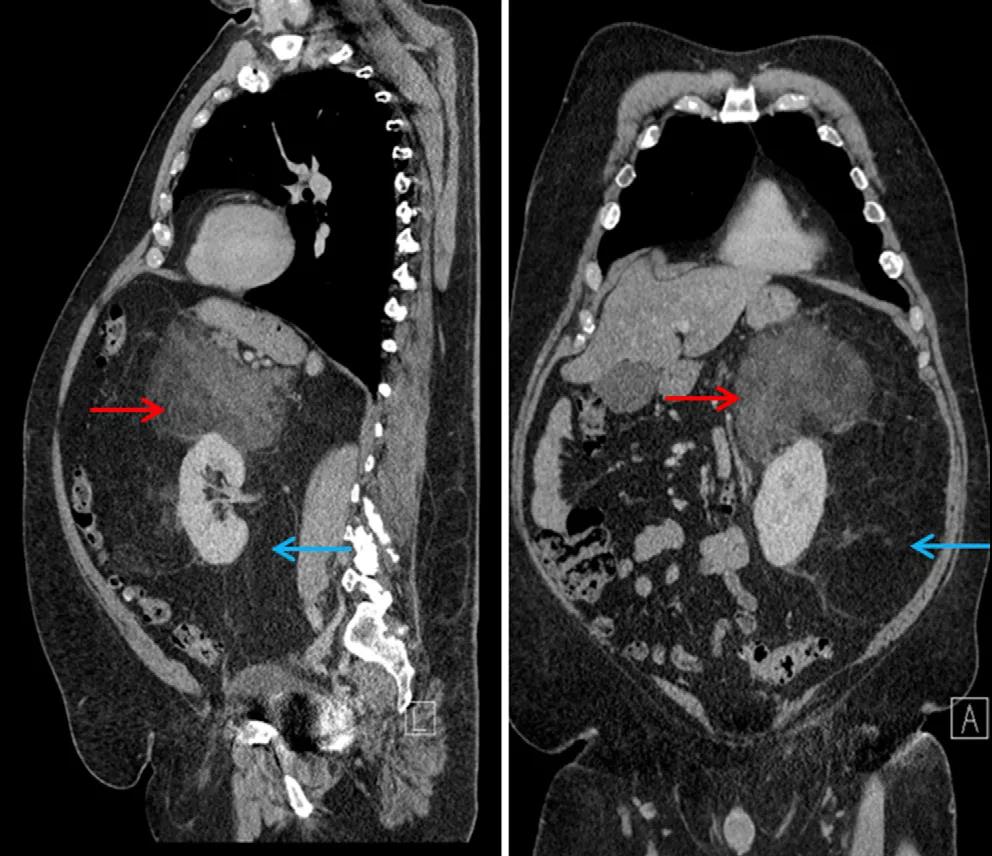

它是由脂肪细胞异常增生导致的,属于软组织肉瘤的一种,可发生在身体的各种脂肪组织,但在腹膜后或者大腿内侧更为常见。脂肪肉瘤会藏的很深,刚开始摸不到。但是长大后变得较硬。

高分化脂肪肉瘤:通常发生在腹膜后或近端出现缓慢增长的肿块,占脂肪肉瘤的50%。通常恶性程度低,一般不会转移,完全切除后预后良好。发生在腹膜后,纵隔或睾丸旁区域时,局部复发更为常见,对化疗和放疗不敏感。

去分化脂肪肉瘤:较罕见,具有高度侵袭性,通常发生在腹膜后。

例如:生长在腹膜后的脂肪肉瘤通常会导致体重减轻、消瘦和腹痛,并且可能由于压迫肾脏与输尿管而导致肾衰竭。

目前的诊断方法一般是通过影像学检查如X射线、CT扫描和MRI(磁共振成像)确定肉瘤的大小和发展程度,其次是通过活检、荧光原位杂交和分子遗传学方法等确定癌细胞类型,并制定相应的诊疗方案。